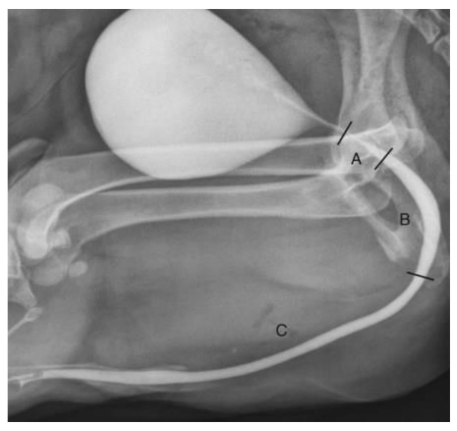

Em cães e gatos machos, o procedimento é realizado inserindo um cateter na uretra peniana distal. Um cateter com ponta de balão (Foley) é preferível em cães, embora um cateter de borracha vermelha também possa ser usado. O bulbo do cateter de Foley é inflado suavemente e deixado inflado por não mais que 15 minutos, porque a pressão excessiva e prolongada pode danificar a uretra. Em gatos machos, um cateter de borracha vermelha ou Tomcat pode ser usado (Fig.2) . Dependendo do tamanho do paciente, uma injeção de 5 a 20 mL de meio de contraste é administrada e radiografias são adquiridas durante a administração dos últimos 1 a 2 mL da injeção. A uretra normal deve ter margens suaves ao longo de todo o seu comprimento. A uretra prostática é mais larga do que a uretra membranosa, embora cada uma possa ter diâmetro variável dependendo do grau de distensão. A uretra peniana tem um diâmetro geralmente uniforme em cães; em gatos, é relativamente estreita. Estreitamento luminal com margens afiladas pode ser visto normalmente no arco isquiático em cães.

(fonte: Brown Jr., Textbook of Veterinary Diagnostic Radiology)

Para a realização do exame contrastado, foi administrado através do catéter uretral o contraste iodado Omnipaque® na dose de 6 ml/kg, diluído na proporção de 1:1 em solução fisiológica seguido da realização de radiografias abdominais sequenciais imediatas e após 5 minutos da administração do contraste.

Através da Uretrocistografia Retrógrada foi visualizado um ponto de extravasamento de contraste para a cavidade abdominal advindo de uretra prostática, porém ainda havendo repleção da vesícula urinária pelo contraste, o que indicava que havia uma ruptura uretral, mas que esta seria parcial.